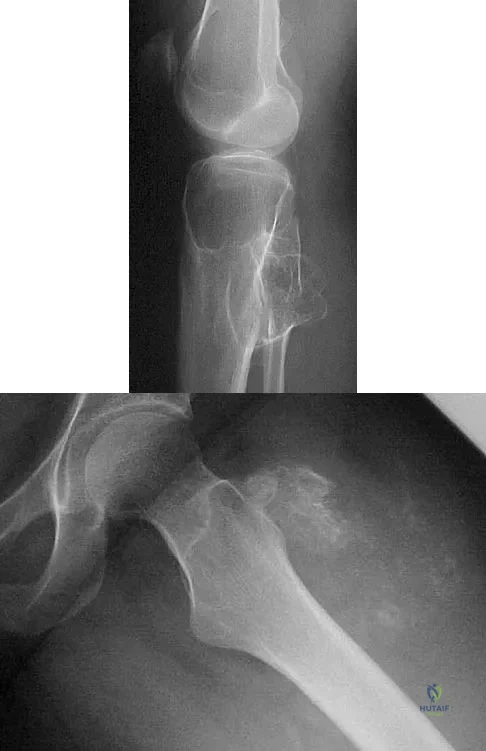

Figures 32a and 32b show the radiographs of a 13-year-old right hand-dominant boy who sustained a closed Salter-Harris type II fracture of the proximal humerus during a hockey game. The shoulder has significant swelling, but is neurovascularly intact. What treatment offers the best chance of reestablishing normal shoulder motion?